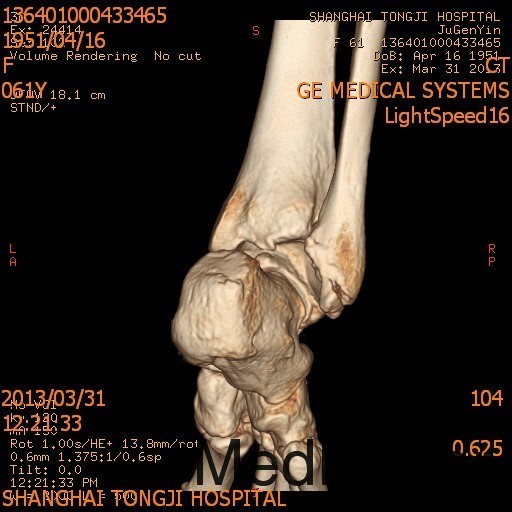

患者女,61岁,摔伤后右踝足肿痛4天。患者4天前不慎摔伤,即感右足踝疼痛,肿胀,活动受限 ,休息后疼痛减轻,X线示右外踝骨折。

诊断为右外踝骨折,完善术前检查后于全麻下行右外踝骨折ORIF术+距腓前韧带修复术。

2年后随访患者活动可,内固定位置可,螺钉未予取出。外踝骨折可导致踝关节不稳定,手术治疗效果可。